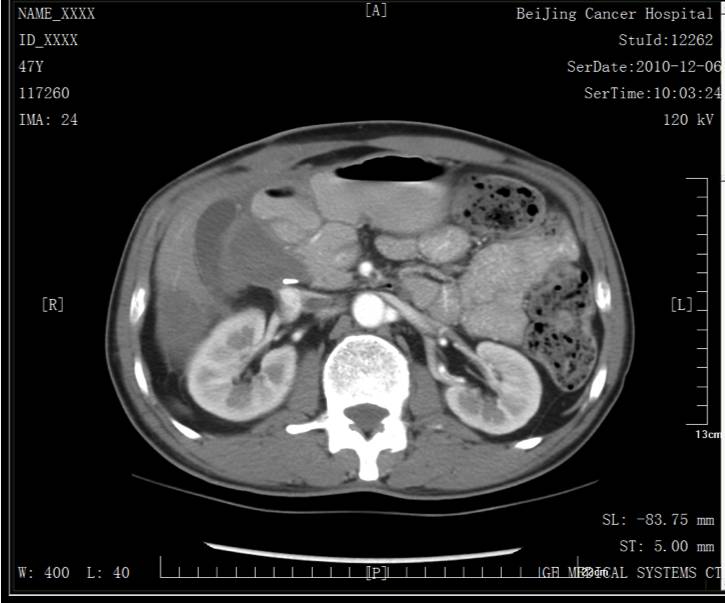

第二次手术(肝+腹膜结节)

2010.02.24在全麻下行右肝部分切除术+腹膜结节切除术。术中探查见肝S6直径约5cm肿物,质硬,邻近肝肾之间腹膜可见结节,大小约3cm。肿瘤完整未见破裂。术后病理:右肝部分S6可见低分化腺癌浸润伴大片坏死,大小7.0x6.0x3.5cm,可见脉管癌栓,切缘未见癌。腹膜结节:可见低分化腺癌,大小3.5x3x1.5cm,结合病史符合结肠癌术后肝及腹膜转移。出院日期2015.03.03。